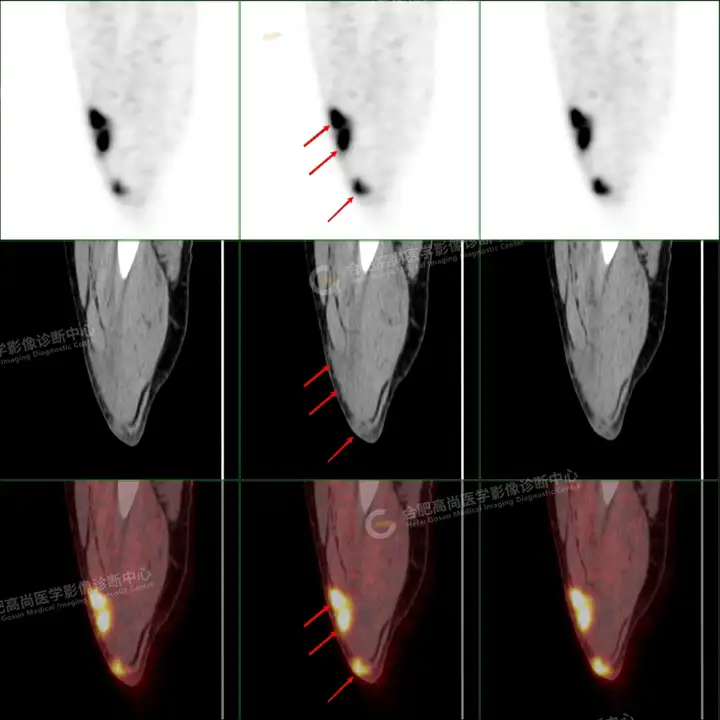

PETCT检查所示:图1、3-17全身多处(双上臂、胸背部、左侧乳腺、左侧腰部、腹壁、双侧臀部及双侧大腿)皮肤下结节及肿块样软组织密度灶,FDG代谢不同程度增高,双侧颈部、左侧锁骨区、纵隔内(1区)及双侧腋窝多发肿大淋巴结,FDG代谢明显增高,符合皮肤来源淋巴瘤。